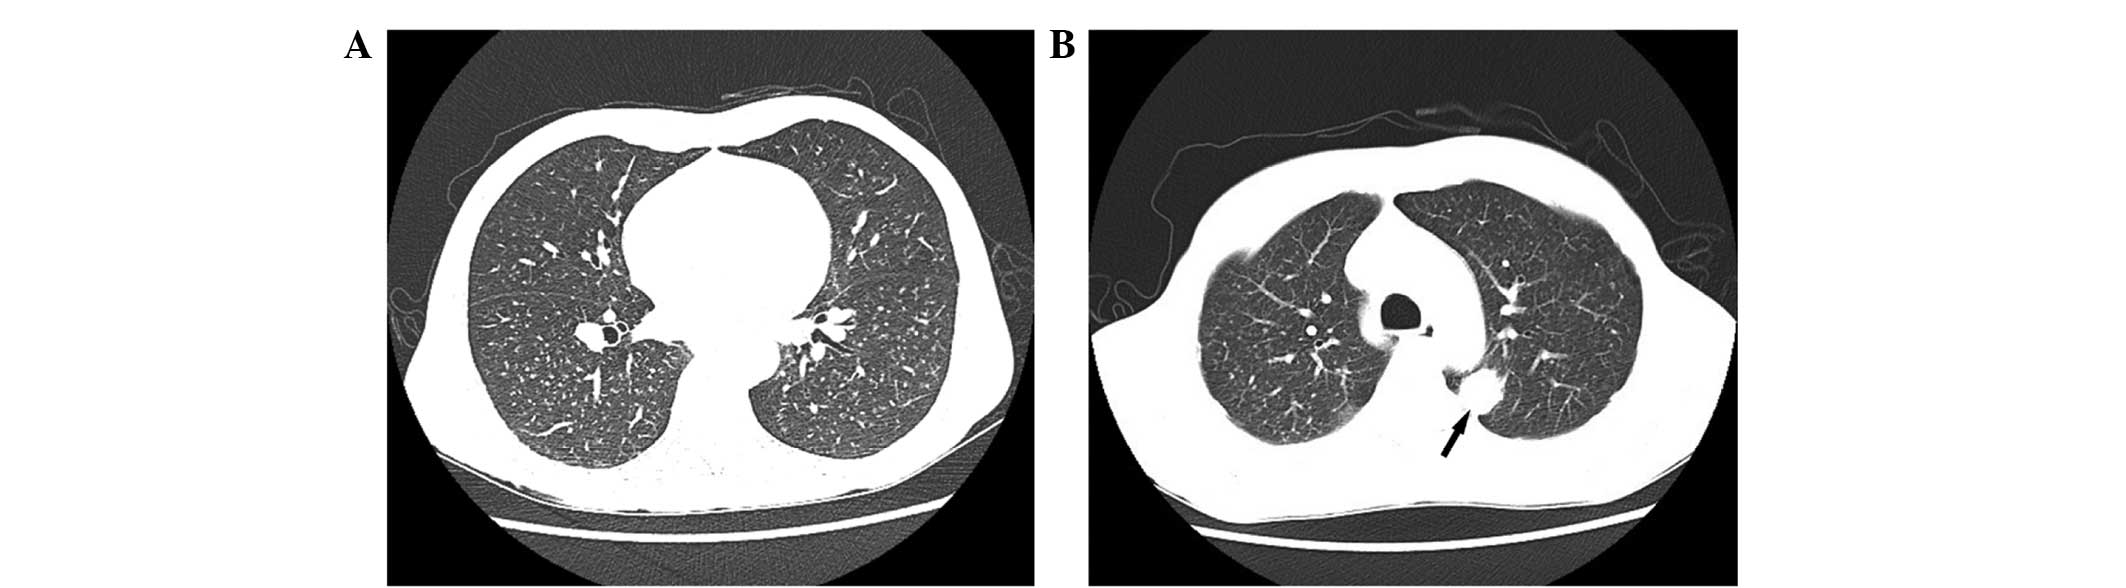

Adrenal sarcomatoid carcinoma is a rare adrenal carcinoma. To the best of our knowledge, only 11 cases have been reported since 1987. Adrenal sarcomatoid carcinoma presents a diagnostic challenge due to its atypical symptoms and histological patterns. At the time of diagnosis, a large percentage of patients are already at the metastatic stage and succumb within a few months. The present study reports a case of a 59‑year‑old man presenting with asthenia and weight loss with adrenal sarcomatoid carcinoma metastatic to the lung. A computed tomography (CT) scan and ultrasonography of the patient's abdomen suggested a large homogeneous mass in the right adrenal gland, and a CT scan of his chest suggested lung metastasis. Right adrenalectomy was performed. Histological examination revealed that the tumor was composed of sarcomatous and carcinomatous differentiation elements. Immunohistochemical examination revealed tumor cell positivity for vimentin and cytokeratin. At the 6‑month follow‑up the patient exhibited no disease progression and refused further proposed treatment. The patient was alive at the time of writing the current report. The present case report additionally reviews the literature, for the purpose of raising awareness of these rare lesions and assisting in achieving accurate diagnoses and effective treatment.